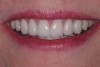

(22.) The final restorations, which reflect the changes modeled through the provisional phase.

Figure 22

Treatment for this patient included posterior reductive equilibration and additive anterior equilibration (restoration) to eliminate the CR/MIP interferences and to meet the requirements of occlusal stability. Teeth Nos. 5 through 11 and 22 through 27 were prepared for full-coverage lithium-disilicate restorations. Crestal bone heights were evaluated. Soft-tissue crown lengthening was performed on the maxillary anterior teeth by a soft-tissue diode as needed. The esthetic, functional, and phonetic changes were evaluated and confirmed in the provisional restorative phase (Figure 17 through Figure 21).

Once approved, impressions of the provisionals were taken so the laboratory could precisely copy the 3D position of the anterior teeth as successfully proven in the provisionals. The postoperative result and final functional photographs are shown in Figure 22 through Figure 29. Posterior treatment can now be completed in segments as necessary. Posterior morphology will be developed in harmony with the now corrected anterior contour and functional parameters. The fulfillment of the previously mentioned requirements of occlusal stability were evaluated and refined in the final restorations. The patient was placed in a posttreatment dual-arch B splint appliance to help manage any further parafunctional forces should they occur.